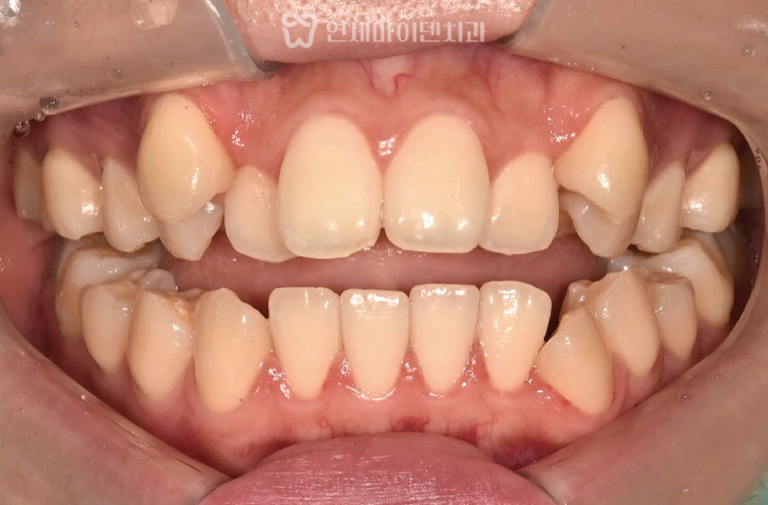

어린이 치아교정 증례: 반대교합 만 7세 어린이의 앞니가 거꾸로 물려조기 교정을 원해 내원한 케이스입니다. 보호자분들 중에는아이의…